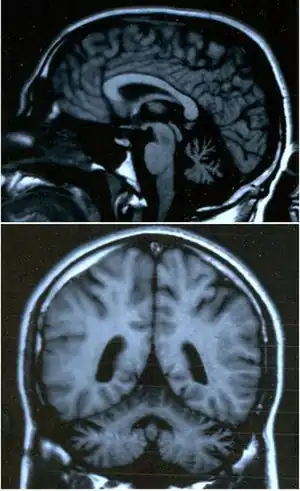

É um sintoma característico de lesão cerebelar, mas também pode aparecer na ataxia de Friedreich, no meduloblastoma e na esclerose múltipla. Frequentemente aparece associada a dificuldade em articular algumas sílabas (disartria).[2]

Acredita-se que seja causada pela dificuldade de ativar e desativar os grupos musculares de forma coordenada devido ao tônus muscular diminuído (hipotonia) resultado de uma lesão do cerebelo ou das vias cerebelosas. Pode ser verificado pedindo ao paciente gire as mãos rapidamente, toque o nariz com o dedo ou bata os pés no chão várias vezes seguidas. A dificuldade em manter ou completar o movimento indica disdiadococinesia. Os pés costumam ter pior desempenho que as mãos.[3] É também causada por intoxicação crônica por fumos metálicos que contenham manganês em sua composição, o que é observado com frequência em soldadores.